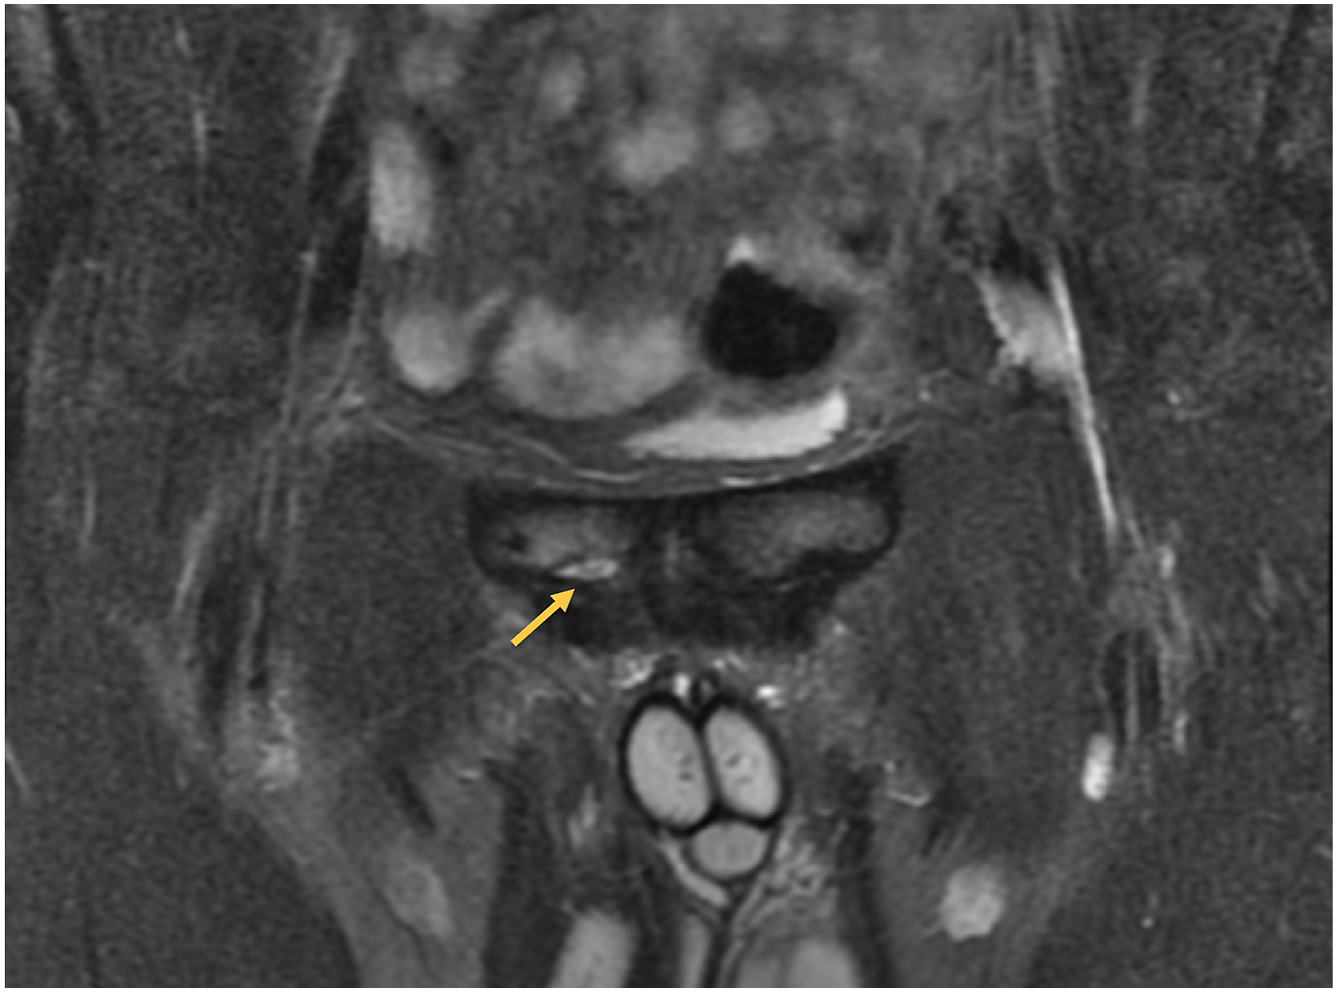

Hip and groin strains

Hip adductor muscle strains are frequently susceptible to injuries from large mechanical loads placed on the small tendon of the adductor longus during muscle contraction. These strains are the most common extra-articular groin injury and are the seventh most common injury in professional baseball with 1156 injuries occurring from 2011 to 2016 resulting in an average of 12.5 days missed per injury ( Fig. 2 ; see Tables 1 and 2 ). Most are acute noncontact injuries resulting from pitching, fielding, or base running with 53.4% occurring in position players. Similarly, Li and colleagues found groin strains to be more common in position players rather than pitchers or catchers. Less than 4% of these injuries were season-ending and only 3% required surgery.